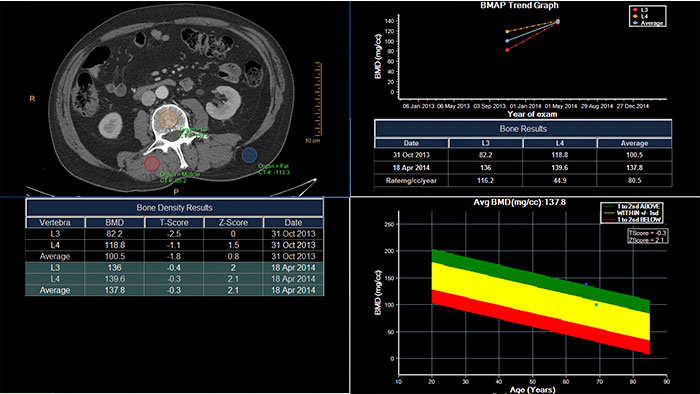

CT Bone Mineral Analysis (BMA)

Track degenerative and metabolic bone disease

CT Bone Mineral Analysis (BMA) is designed to measure bone density in one or multiple time points. Using an internal reference method*, the application reduces reproducibility errors in multiple time point measurements and provides T- and Z- scores which help physicians assess the risk of osteoporosis.

• The user can compare a patient’s results to several reference populations.

*Muller DK, et al., Phantom-less QCT BMD system as screening tool for osteoporosis without additional radiation. Eur J Radiol. 2011; 79(3):375–81.